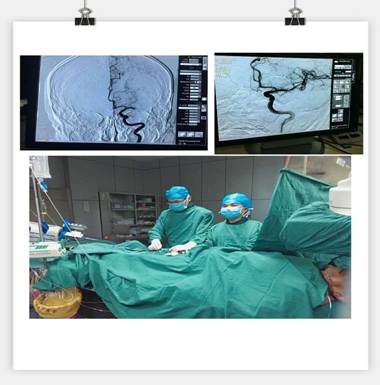

通訊員劉巧報(bào)道:10月21日,我院神經(jīng)內(nèi)科成功實(shí)施靜脈溶栓聯(lián)合血管內(nèi)介入治療的橋接搶救,成功救治了一位意識(shí)障礙的大面積腦梗塞的患者。

凌晨3點(diǎn)30分, “叮叮叮”一陣急促的電話響鈴打破了深夜的寧?kù)o。 “你好,這里是急診科,請(qǐng)準(zhǔn)備一張男床,腦血管意外患者”。患者是一名63歲男性,突發(fā)右側(cè)肢體乏力5.5小時(shí),由家屬用輪椅推送入院。入科后患者神志昏睡,心率48次/分,血壓186/100mmHg,NIHSS評(píng)分20分。病人情況十分危急,在劉禮泉主任指示下,患者為急性缺血性卒中,有溶栓指征。在劉主任與家屬談話期間,值班醫(yī)生同時(shí)開(kāi)出醫(yī)囑,患者予以硝普鈉控制血壓+尿激酶靜脈溶栓。夜班護(hù)士立即給病人抽血、吸氧、心電監(jiān)護(hù)、建立靜脈通道、準(zhǔn)備藥物……我們忙而不亂,默契配合。溶栓過(guò)程中劉主任一直守護(hù)在病人身旁,隨時(shí)觀察病人的病情變化。溶栓后,患者右側(cè)肢體有自主活動(dòng),但乏力癥狀及意識(shí)障礙無(wú)明顯緩解,劉主任立即決定行頭頸聯(lián)合CTA,明確是否有大血管閉塞。果不其然,患者頭部CTA提示左側(cè)大腦中動(dòng)脈M1段栓塞,如果大血管得不到及時(shí)開(kāi)通,必然會(huì)出現(xiàn)災(zāi)難性的后果。劉主任建議家屬考慮是否行血管內(nèi)治療開(kāi)通血管,經(jīng)過(guò)耐心細(xì)致的溝通,患者家屬同意行急診腦血管造影檢查及血管內(nèi)治療。 同時(shí)立即召集曾比賢副主任、聶利珞副主任趕來(lái)醫(yī)院,為患者在局麻下行全腦血管造影+顱內(nèi)血管取栓術(shù)。時(shí)間伴隨著沉悶緊張的氣氛一分一秒地過(guò)去,取栓的生命通道終于打開(kāi),患者病變血管恢復(fù)良好,手術(shù)圓滿成功,此時(shí)灰暗的天才微微光亮……

在急性腦梗死患者緊急救治中,時(shí)間就是生命,該病例運(yùn)用了動(dòng)靜脈聯(lián)合的方式治療急性腦梗塞,有效地保護(hù)了患者的大腦,此類技術(shù)在國(guó)內(nèi)處于領(lǐng)先治療手段,溶栓、取栓同步進(jìn)行的橋接搶救措施起到了至關(guān)重要的作用。該病例成功取栓意味著我院神經(jīng)內(nèi)科在治療急性腦血管病方面已經(jīng)從傳統(tǒng)的靜脈溶栓向介入取栓的現(xiàn)代化治療方式轉(zhuǎn)變。